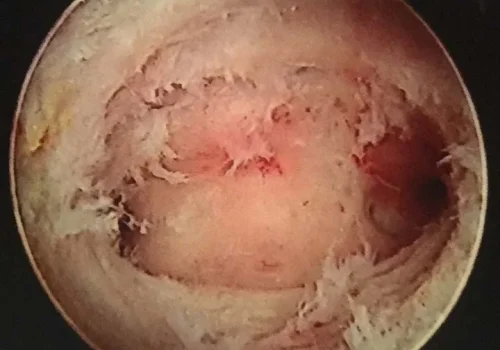

Asherman’s Syndrome - Hysteroscopy

Imaging of the uterine cavity (sonohysterogram) revealed significant intra-uterine adhesions (Asherman’s Syndrome).

These were divided at Hysteroscopy. The pathology revealed placental elements.